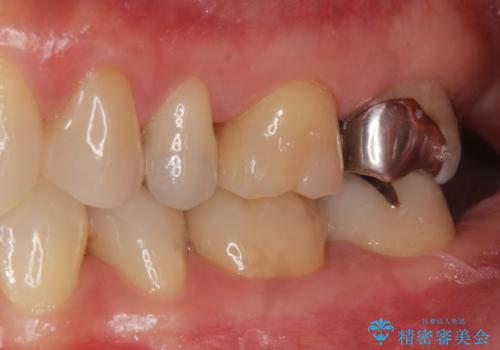

- 銀歯を無くしたいとの事で来院。

拡大鏡下でメタルを除去し虫歯がないことを確認してから白い詰め物、被せ物で治療を行いました。

- ジルコニアクラウンスタンダード・仮歯 12.1万円 e-maxインレー・7.7万円費用は治療当時の料金となります

適合の良い詰め物、被せ物が入りました。